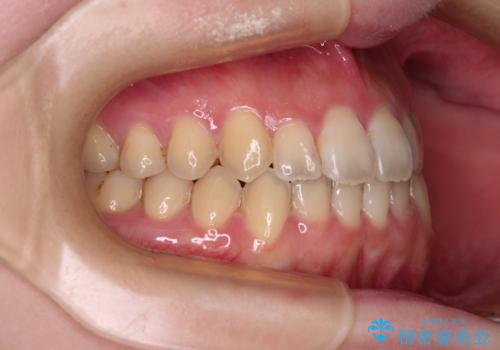

オープンバイトと前歯のデコボコをインビザライン矯正で解消

- 前歯の開咬を気にして来院された患者様です。

開咬の治療は、前歯を閉じるように動かすとともに、上下臼歯を圧下(骨内にめり込ませる)させることで進めて行きます。

インビザラインは臼歯の圧下を効果的に行えるため、インビザラインを用いて矯正治療を行うこととしました。